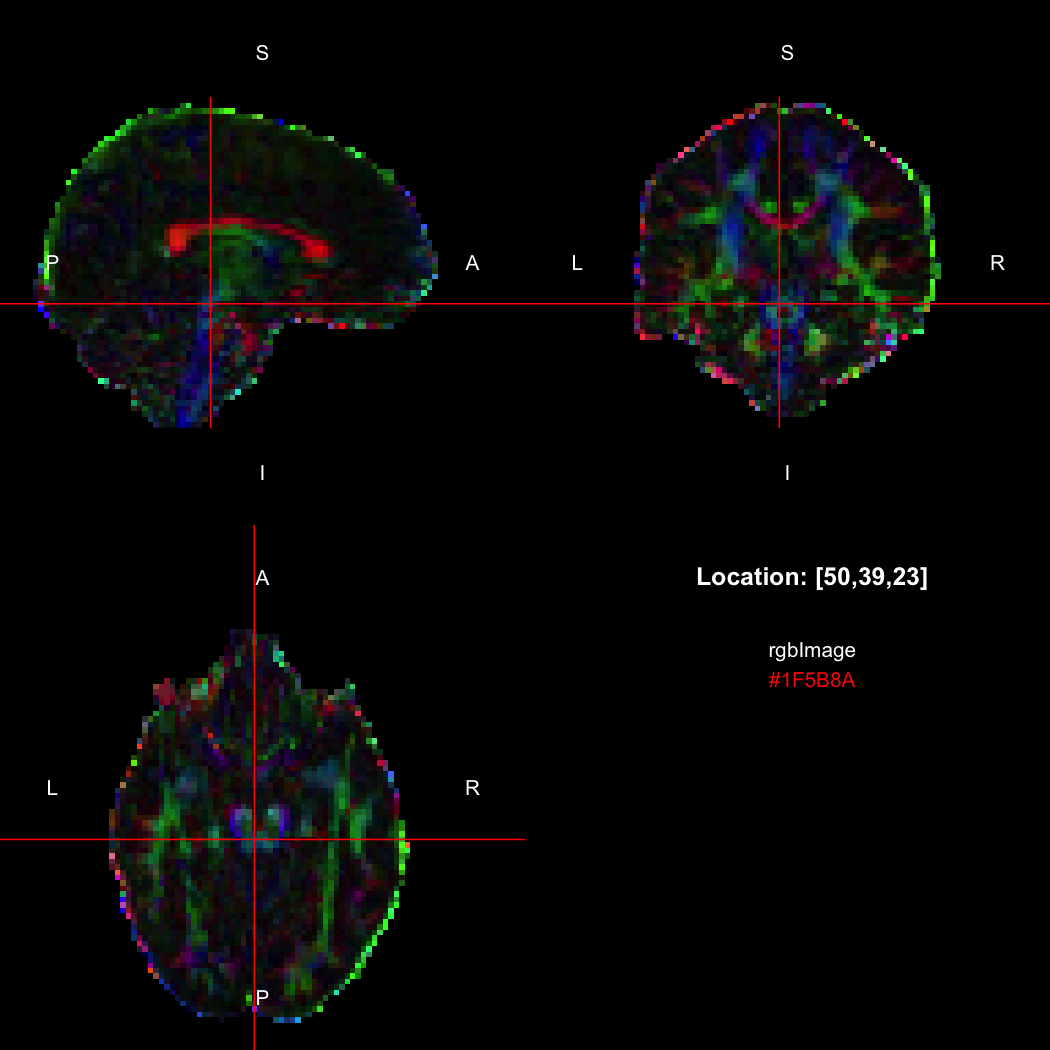

## [1] 300+0iR’s native representation for RGB values is CSS-style hex

strings of character mode, which are reasonably space-efficient (8

or 10 bytes per value) but a little clunky to work with. For efficiency

of interchange between R and the NIfTI-internal datatypes,

RNifti uses a byte-packed representation of integer mode

instead, which takes up 4 bytes per value. Of course, the viewer

understands this format.

rgbImage <- readNifti(system.file("extdata", "example_rgb.nii.gz", package="RNifti"))

print(rgbImage)

## Image array of mode "integer" (2.1 Mb)

## - 96 x 96 x 60 voxels

## - 2.5 x 2.5 x 2.5 mm per voxel

class(rgbImage)

## [1] "niftiImage" "rgbArray" "array"

view(rgbImage)

Notice that values are shown in the viewer using R’s conventional hex

string format, but the data is of class rgbArray. The

function of the same name can be used to create these arrays from

strings or channel values, for the purposes of building RGB images from

data, while the as.character method and

channels function perform the opposite conversions.

as.character(rgbImage, flatten=FALSE)[50,39,23]

## [1] "#1F5B8A"